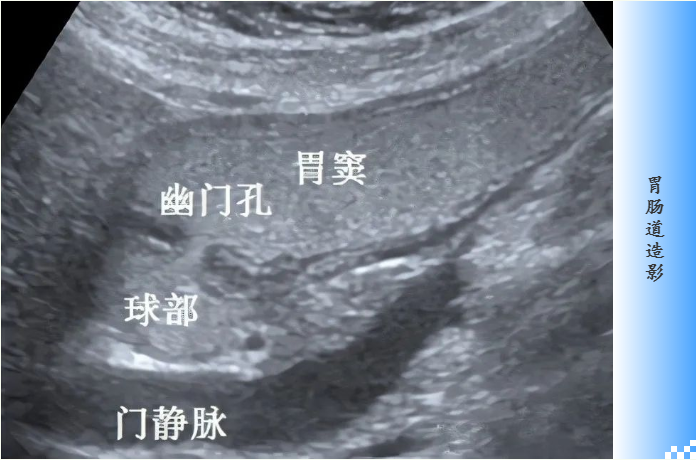

临床上,需要对消化道、泌尿系、心血管等的病变部位进行检查时,可使用X线造影进行辅助检查。

在进行X线造影之前,需要通过服用或灌肠等方法导入造影剂,使密度差别特别小的器官或组织产生明显对比而显影。

X线造影剂密度会高于或低于人体软组织,因此在X线照射下,其显影密度与周围组织形成明显的差异,由此可观察人体器官形态和功能是否正常。

由于硫酸钡能吸收较多量X线从而阻断X线透过,在进入胃肠道后,它会与周围组织结构在X线图像上形成密度对比,从而显示出这些腔道的位置、轮廓、形态、表面结构和功能活动情况。